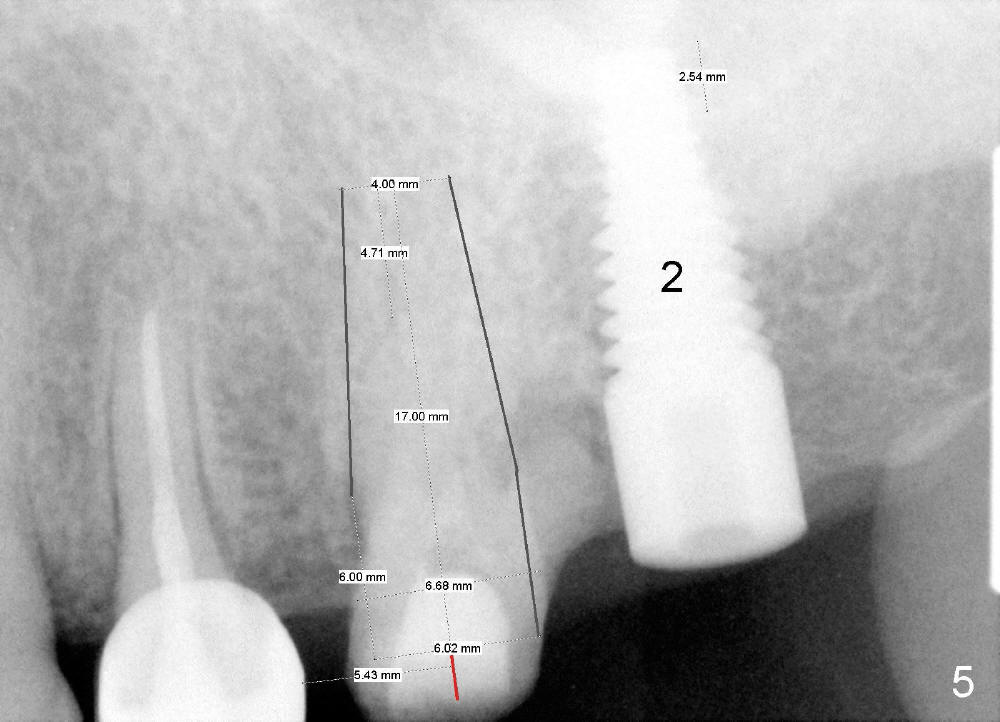

In fact, the implant at the 1st molar is planned to be placed 5.5 mm from the distal surface of the 2nd premolar (Fig.5). When the 1st intraop PA is taken with a 4.5x20 mm tap (Fig.6: T), the deviation is not noted (Fig.6: 7.5 mm vs. 5.5 mm in Fig.5). The trajectory of the implant (5x20 mm) remains deviated (Fig.7).